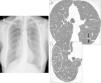

A) La radiografía de tórax posteroanterior presenta un patrón intersticial micronodular bilateral y difuso. B) Las imágenes de la TACAR torácica muestran patrón en tree-in-bud, consistente en estructuras ramificadas (flechas negras) y brotes (flechas blancas). C) Visión más amplia con abundantes brotes periféricos (C: círculo).

Presentamos el caso clínico de una mujer 56 años, de raza caucásica, que nunca ha sido fumadora y sin historia familiar, laboral y farmacológica destacable. Refiere desde hace 2años tos persistente productiva diaria y disnea de moderados esfuerzos. En el examen físico destacan crepitantes secos bibasales. Los datos analíticos básicos eran normales, a excepción de un factor reumatoide de 53UI/ml (normal, <20 UI/ml) y de inmunoglobulinaA de 484mg/dl (normal, 82-453mg/dl). La radiografía de tórax muestra pequeñas opacidades nodulares bilaterales, y la tomografía axial computarizada de tórax de alta resolución (TACAR), patrón en tree-in-bud (fig. 1). La espirometría revela un patrón restrictivo leve, y el test de marcha de 6min muestra caída de la saturación arterial de oxígeno del 98 al 90%. El ecocardiograma fue normal. El lavado bronquioalveolar muestra neutrófilos (87%) e índice CD4/CD8 de 1,16, y la biopsia transbronquial no mostró alteraciones. Ante la ausencia de un diagnóstico definitivo, se realiza una biopsia pulmonar quirúrgica (BPQ). El estudio anatomopatológico reveló inflamación crónica localizada principalmente en los bronquíolos respiratorios, con linfocitos, células plasmáticas e histiocitos espumosos; en las luces bronquiolares se veían predominantemente neutrófilos. Todos estos datos histológicos encuadran con el diagnóstico de PD. Se inicia tratamiento con claritromicina vía oral (250mg/12h), y durante los primeros 6meses de seguimiento la paciente presenta buena tolerancia al tratamiento prescrito, aunque persisten los síntomas iniciales.